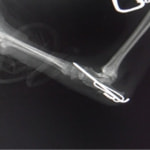

症例:交通事故による椎体脱臼

柴犬:9歳、避妊雌

交通事故直後、胸腰部に激しい疼痛、両後肢に完全麻痺を認め、シェフシェリントン徴候を呈していました。レントゲン検査において、第11-12胸椎間の脱臼が認められました。

脊髄の減圧、脊柱管の再構築・安定化を目的に、片側椎弓切除術およびMatrixMANDIBLE Plateによる椎体固定を実施しました。

隣接椎体を架橋するようにプレートを設置しました。

術後レントゲン写真